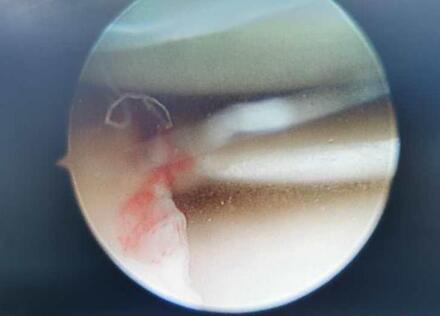

红星新闻记者从温江区人民医院骨科主治医师胡兵处了解到,冯某东右膝关节外侧半月板撕裂,“撕裂得比较厉害,前天已经做了手术。”胡兵表示,冯某东接下来需要进行康复治疗,但恢复的时间不好估计。

↑冯某东半月板撕裂。

“要恢复正常生活,乐观点需要两三个月,但时间有可能更长,甚至半年。”胡兵说,目前冯某东的治疗费用已有3万多元,“后续费用不好估计,康复治疗和基础护理等大概需要两三百块一天。”